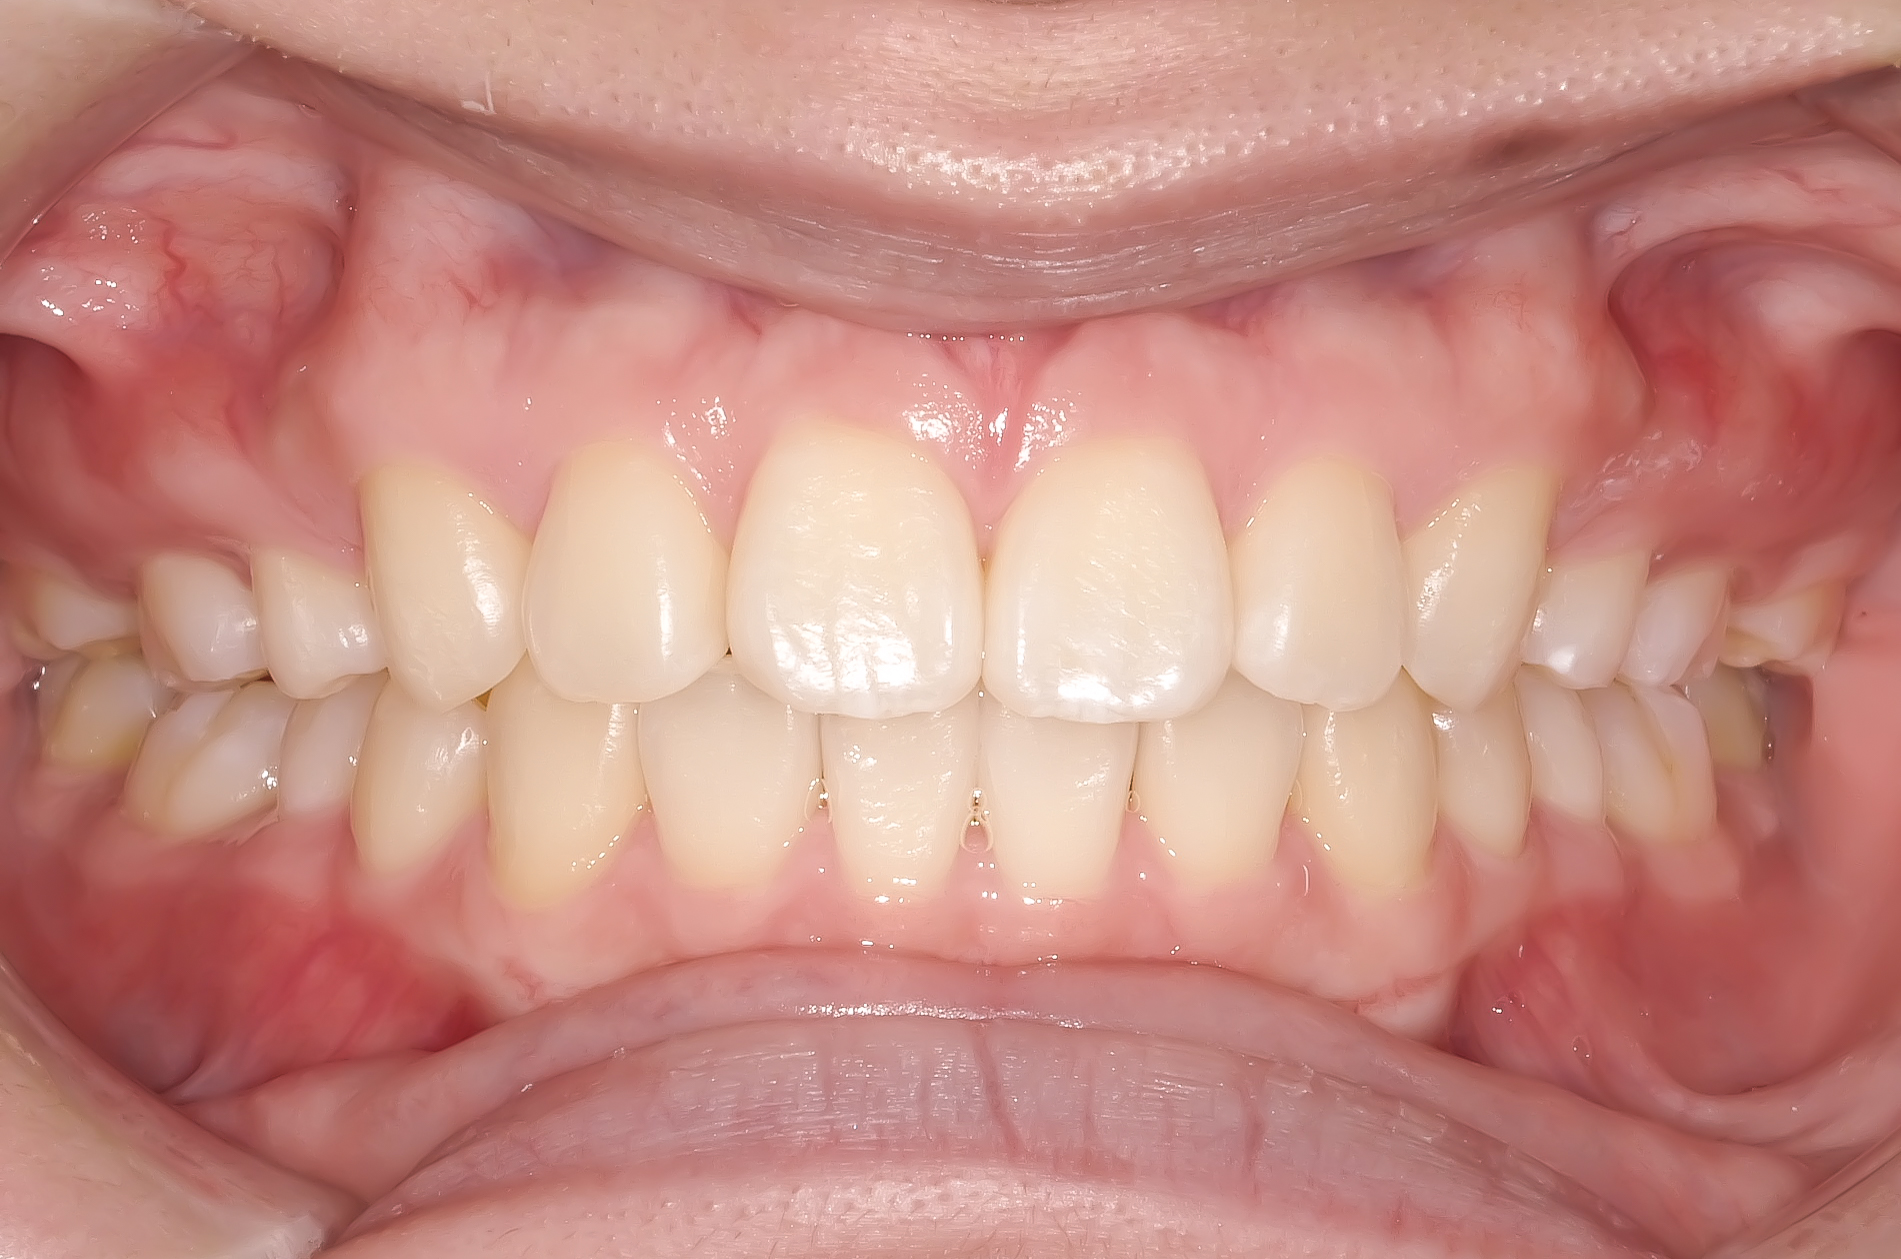

治療終了時の写真です。

上下の歯の真ん中が揃い、きれいに並んでいます。